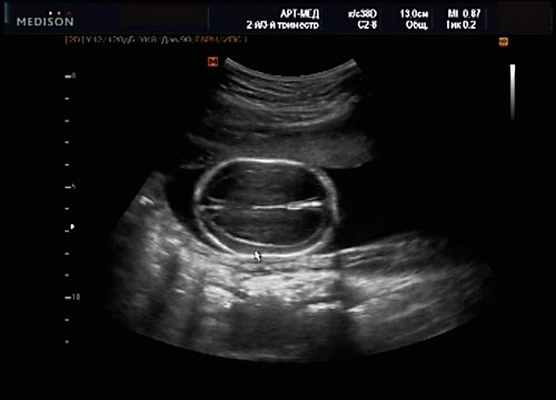

Клиническое наблюдение 1

Пациентка К., 26 лет, обратилась в клинику в 23 нед беременности. Беременность первая. Исследование проводилось на аппарате Accuvix-XQ (Samsung Medison) с использованием режима поверхностной объемной реконструкции 3D/4D. Показатели фетометрии полностью соответствовали сроку беременности. В процессе сканирования позвоночника во фронтальной и сагиттальной плоскостях выявлена угловая деформация позвоночника в грудном отделе, протяженностью около трех позвонков. В поперечной плоскости сканирования нарушения структур и целостности тканей не было обнаружено. В режиме 3D/4D реконструкции было выявлено асимметричное расхождение ребер правой и левой стороны грудной клетки (рис. 4).